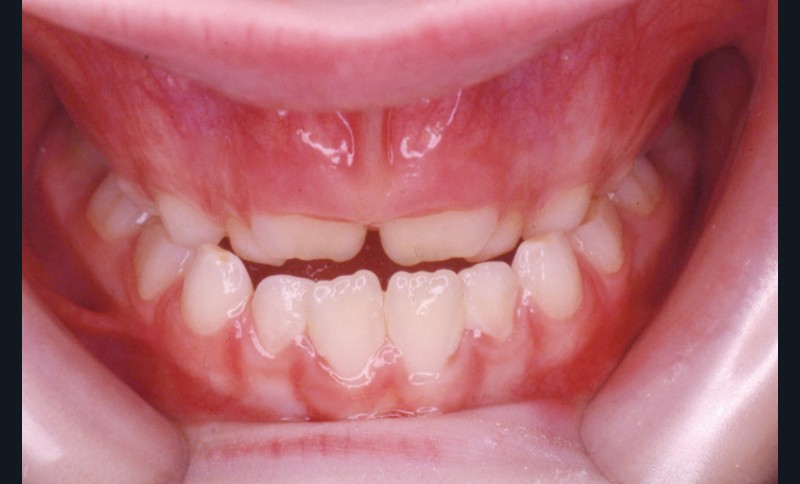

L’examen de la denture (fig. 3 à 5) montre :

• dans le sens antéro-postérieur, des relations molaires et canines de type classe III d’Angle et une inversion des rapports incisifs,

• dans le sens transversal, une endomaxillie bilatérale prédominante dans la région canine.